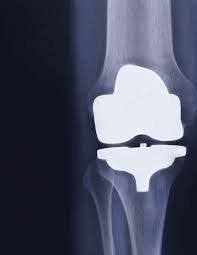

Knee Surgery GET IN TOUCH Knee Arthritis Meniscal Tears ACL Tears Knee Instability The Painful Or Failing Knee Replacement Radio Frequency Ablation Learn MOre Knee Arthroscopy Learn MOre ACL Reconstruction Learn MOre Partial Knee Replacement Learn MOre Total Knee Replacement Learn MOre PSI | KA | TOTAL KEE REPLACEMENT Learn MOre ROBOTIC-ASSISTED TKA Learn MOre REVISION KNEE REPLACEMENT Learn MOre KNEE CONDITIONS Learn MOre OUR SERVICES If joint pain or injury is affecting your daily life, Dr Paterson is here to support your recovery with individualised, evidence-based care. Radio Frequency Abolation (Knee) Learn MOre Knee Arthroscopy Learn MOre Anterior Cruciate Ligament (ACL) Reconstruction Learn MOre Partial Knee Replacement Learn MOre Total Knee Replacement Main Menu LEARN MORE Total Knee Replacement Surgery PATIENT SPECIFIC, KINEMATICALLY ALIGNED TOTAL KNEE REPLACEMENT ROBOTIC-ASSISTED TOTAL KNEE REPLACEMENT REVISION KNEE REPLACEMENT SURGERY LEARN MORE TOTAL KNEE REPLACEMENT PATIENT SPECIFIC (PSI), KINEMATICALLY ALIGNED TOTAL KNEE REPLACEMENT ROBOTIC-ASSISTED TOTAL KNEE REPLACEMENT REVISION KNEE REPLACEMENT SURGERY